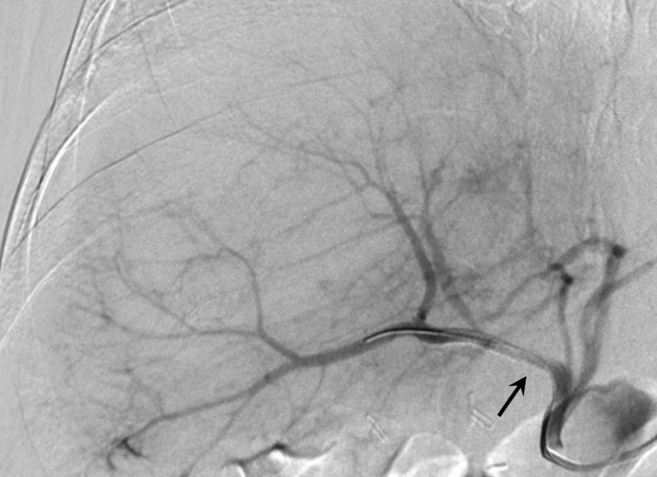

복강동맥조영술에서 우간동맥의 분지부에 인접한 위치에 가성동맥류를 확인하였다(Fig. 2A, B). 6F Shuttle guiding catheter(Cook, Bloomington, IN, USA)로 교체 후에 Stent-graft(4×26mm, JoStent GraftMaster®, JoMed, Germany)를 가성동맥류가 있는 우간동맥에 위치시키고, 풍선카테터(Ultra-thin Diamond,Boston Scientific, Galway, Ireland)를 사용하여 확장시켰다. 시술 직후 시행한 복강동맥조영술에서 동맥류는 관찰되지 않았다(Fig. 2C).

Fig. 2

Celiac (A) and hepatic angiogram (B) show the pseudoaneurysm (arrows in A and B) at distal part of the right hepatic artery near the origin of the right posterior hepatic artery. (C) On hepatic angiogram after stent-graft placement (arrow), the pseudoaneurysm is completely excluded.